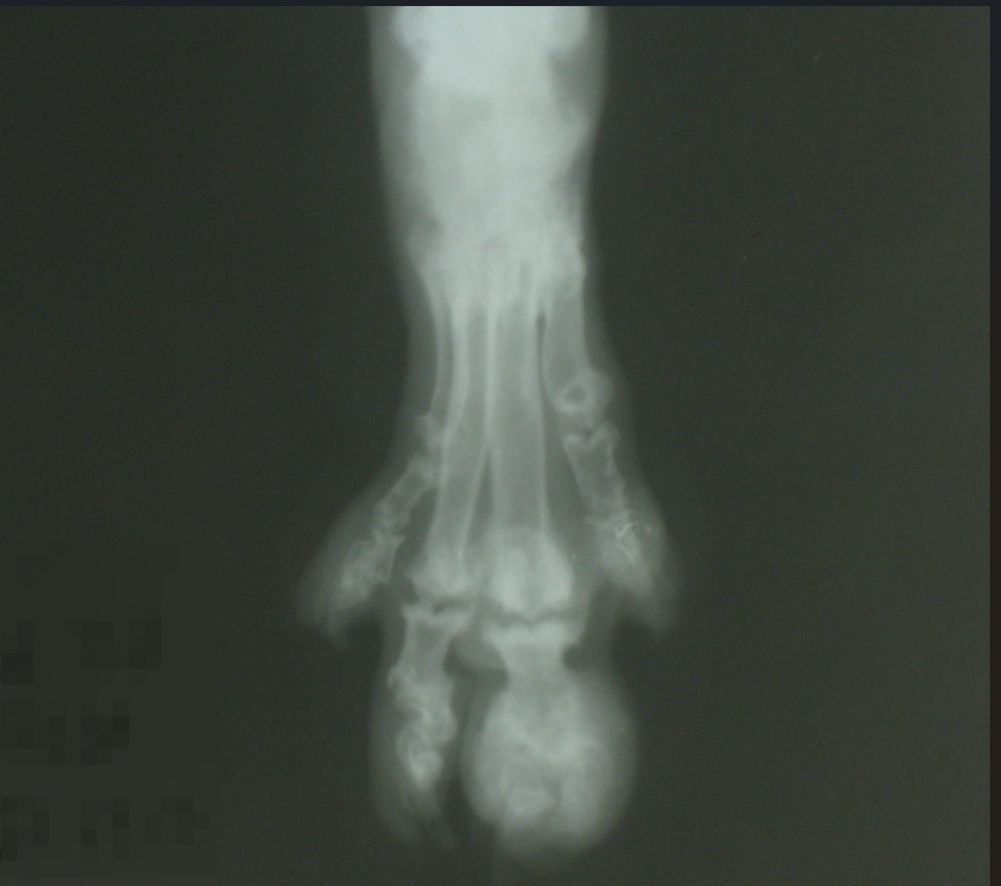

Самое известное заболевание скоттиш-фолдов — остеохондродисплазия. Выглядит она вот так:

Остеохондродисплазия у шотландской вислоухой кошки

Это — лайт-версия, у животного на момент осмотра была поражена только одна лапа. В профессиональных пабликах мне встречались рентгенографии позвоночника жертв вязки фолд+фолд, и это воплощённая боль.